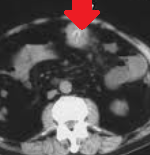

Παρουσία αέρα στο πυλαίο φλεβικό σύστημα, δευτεροπαθώς σε ισχαιμική κολίτιδα (Ευγενική παραχώρηση Dr. V. Penopoulos)